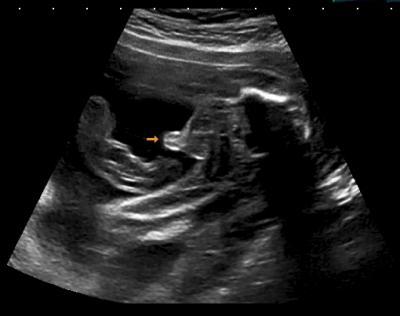

huhu ihr lieben, ich komme gerade zurück von der feindiagnostik. mit dem krümel ist alles okay. 24cm und 411 g. es ist auch immer noch ein junge (siehe bild) zwei dinge waren auffällig: - die rechte umbivikalvene (= verbindung von nabelschnur und fötus) und nicht die linke sorgt für die versorgung des babys. das ist nichts krankhaftes, sondern eine anatomische kuriosität. wir bekommen ein echtes individuum - es exisiterte eine kleine zyste in der niere, die in der rückbildung ist. ist auch nix zum sorgen machen, wird keine beschwerden verursachen, wüsste man ohne die modernen geräte überhaupt nicht. achja, ich hab in das teure designwaschbecken des doktors gespuckt. er hat es mit fassung getragen ... und ich bin über den zustand hinaus, in dem mir so etwas noch peinlich wäre... lg maren

Bild zu zurück von der feindiagnostik - Forum für April - Mamis

Hallo Maren, Das ist ja mal ein schönes eindeutiges Bild! auf so eines hoffe ich auch am Montag..... Schön, dass es deinem Krümel so gut geht und er wächst und gedeiht und die Befunde soweit in Ordnung sind. Mein Kleinster hatte Plexuszysten im Gehirn, die aber auch im Laufe der folgenden US Untersuchungen wieder verschwunden sind.....mir wurde damals auch gesagt, dass es nichts außergewöhnliches ist! Trotzdem tuts mir leid, dass dir so übel war......hoffe dir gehts bald besser! Liebe Grüße Sonja